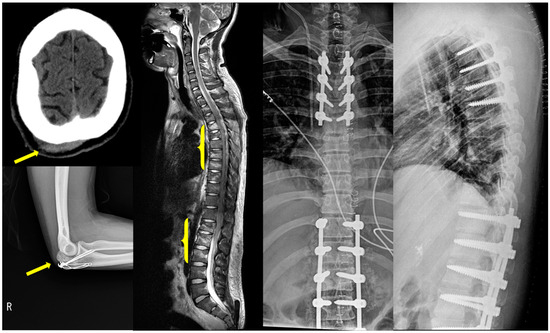

2. Case Description